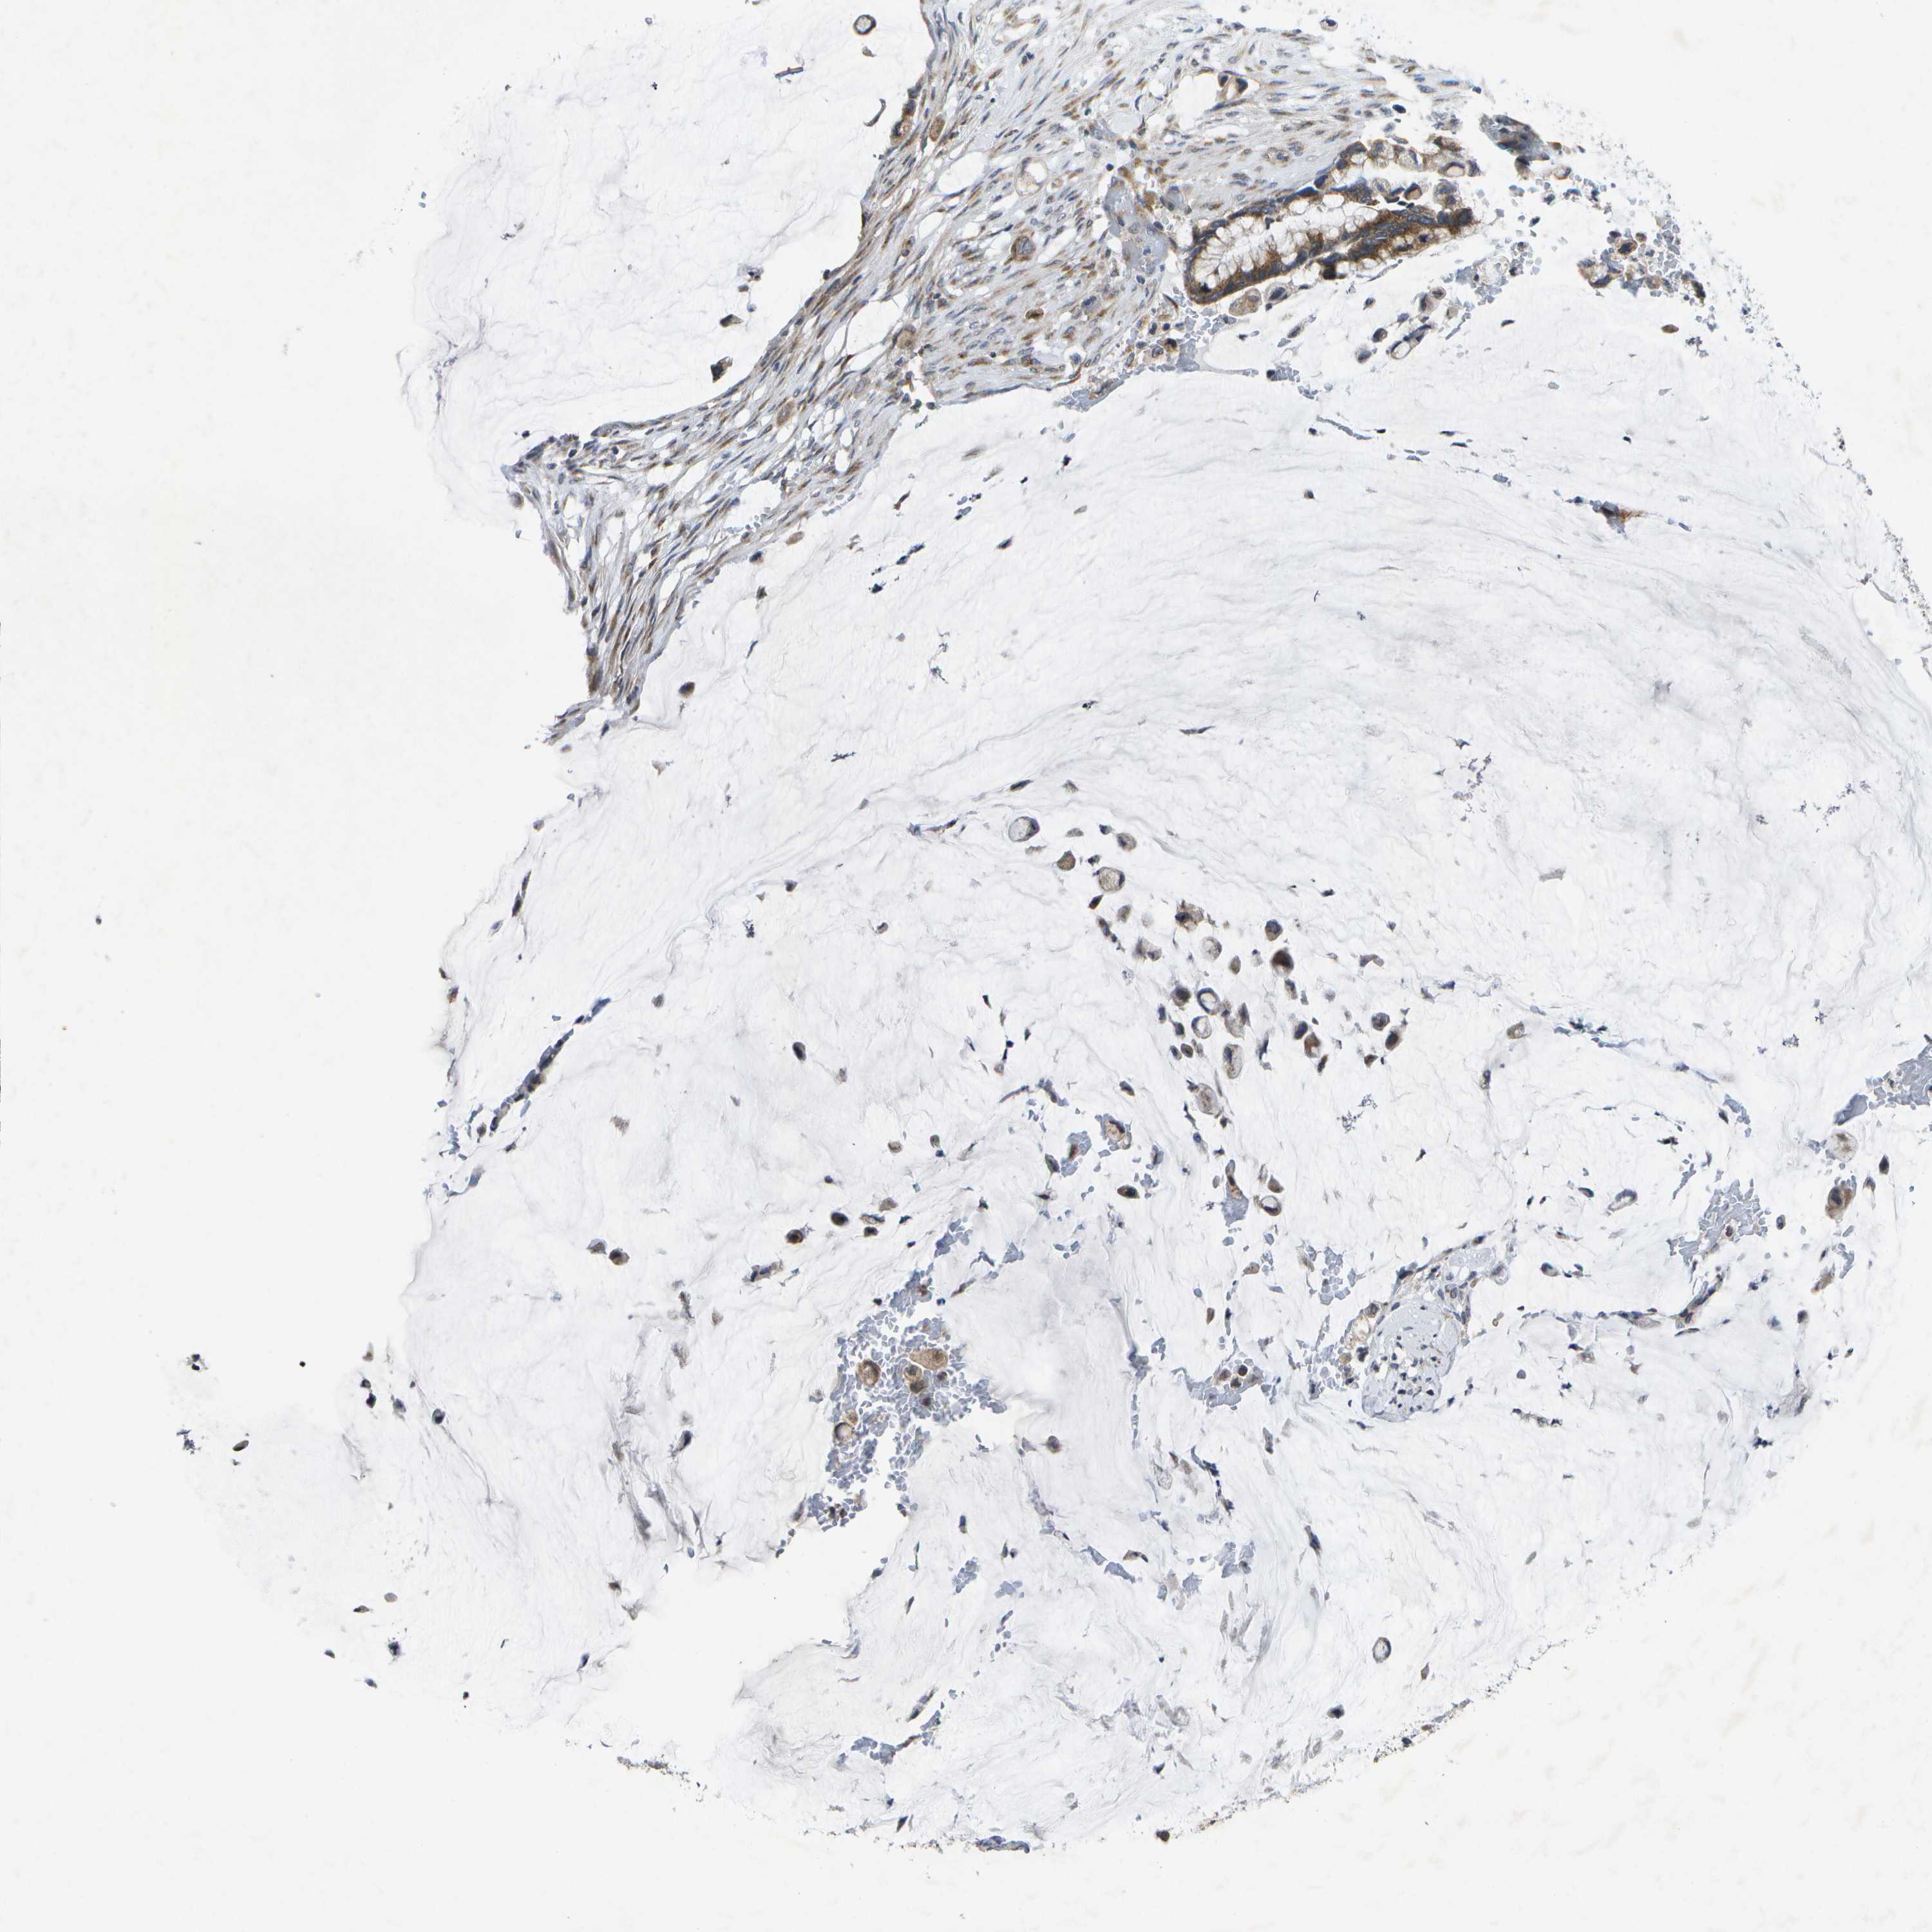

PANCREATIC CANCER - Protein expressioni

A mouse-over function shows sample information and annotation data. Click on an image to view it in a full screen mode. Samples can be filtered based on level of antibody staining by selecting one or several of the following categories: high, medium, low and not detected. The assay and annotation is described here.

Note that samples used for immunohistochemistry by the Human Protein Atlas do not correspond to samples in the TCGA dataset.

Antibody stainingi

Antibody staining in the annotated cell types in the current human tissue is reported as not detected, low, medium, or high, based on conventional immunohistochemistry profiling in selected tissues. This score is based on the combination of the staining intensity and fraction of stained cells.

Each image is clickable and will lead to virtual microscopy that enables deeper exploration of all samples and also displays staining intensity scores, fraction scores and subcellular localization as well as patient and tissue information for each sample.

Antibody CAB017455

Staining

High

Medium

Low

Not detected

Intensity

Strong

Moderate

Weak

Negative

Quantity

>75%

75%-25%

<25%

None

Location

Nuclear

Cytoplasmic/membranous

Cytoplasmic/membranous,nuclear

Adenocarcinoma, NOS